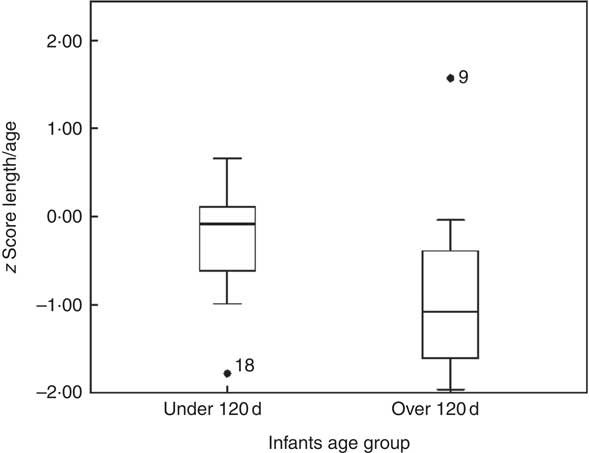

In infants younger than 120 d, LAZ was −0·3 (sd 0·7) (1/9<−1, 4/9 between −1 and 0, 4/9 between 0 and +1), and in infants older than 120 d it was −0·8 (sd 1·1) (6/9 between −2 and −1, 2/9 between −1 and 0 and 1/9>+1). This is illustrated in the box plot in Fig. 2. In the younger group, one infant was mildly stunted (LAZ <−1), but in the older group 6 infants had LAZ <−1. Because of the small group size, LAZ was not normally distributed, and thus we decided to use non-parametric statistics, finding a significant difference (P=0·009), with the older group showing signs of growth faltering.

Fig. 1 z Score length/age by age groups.

A moderate positive association was found between human milk intake and weight-for-length z score, r 0·58 (P=0·01), BMI-for-age z score, r 0·56 (P=0·01), and weight-for-age z score, r 0·45 (P=0·05) as shown in Fig. 3. There was no correlation between human milk intake and LAZ, as shown in Fig. 2–3. No associations were found between infant size and intake of water from non-human milk sources.

In this study, linear growth faltering was apparent in the older infants (>120 d). This tendency has been described earlier in infants from Bolivia; in a retrospective study using data from infant growth charts, infants at 4 months of age showed signs of stunting( Reference Tapia, San Miguel and Urteaga 36 ). In the 1990s, a randomised trial in developing countries evaluated early complementary food intake by 4-month-old breast-fed infants. In Bolivia, there was no effect on stunting. Even in the control group, the LAZ went from −1·0 at 4 months to −1·5 at 7 months( Reference Simondon, Gartner and Berger 16 ). Stunting is a sign of cumulative deficiencies in health and nutrition of a child long term.